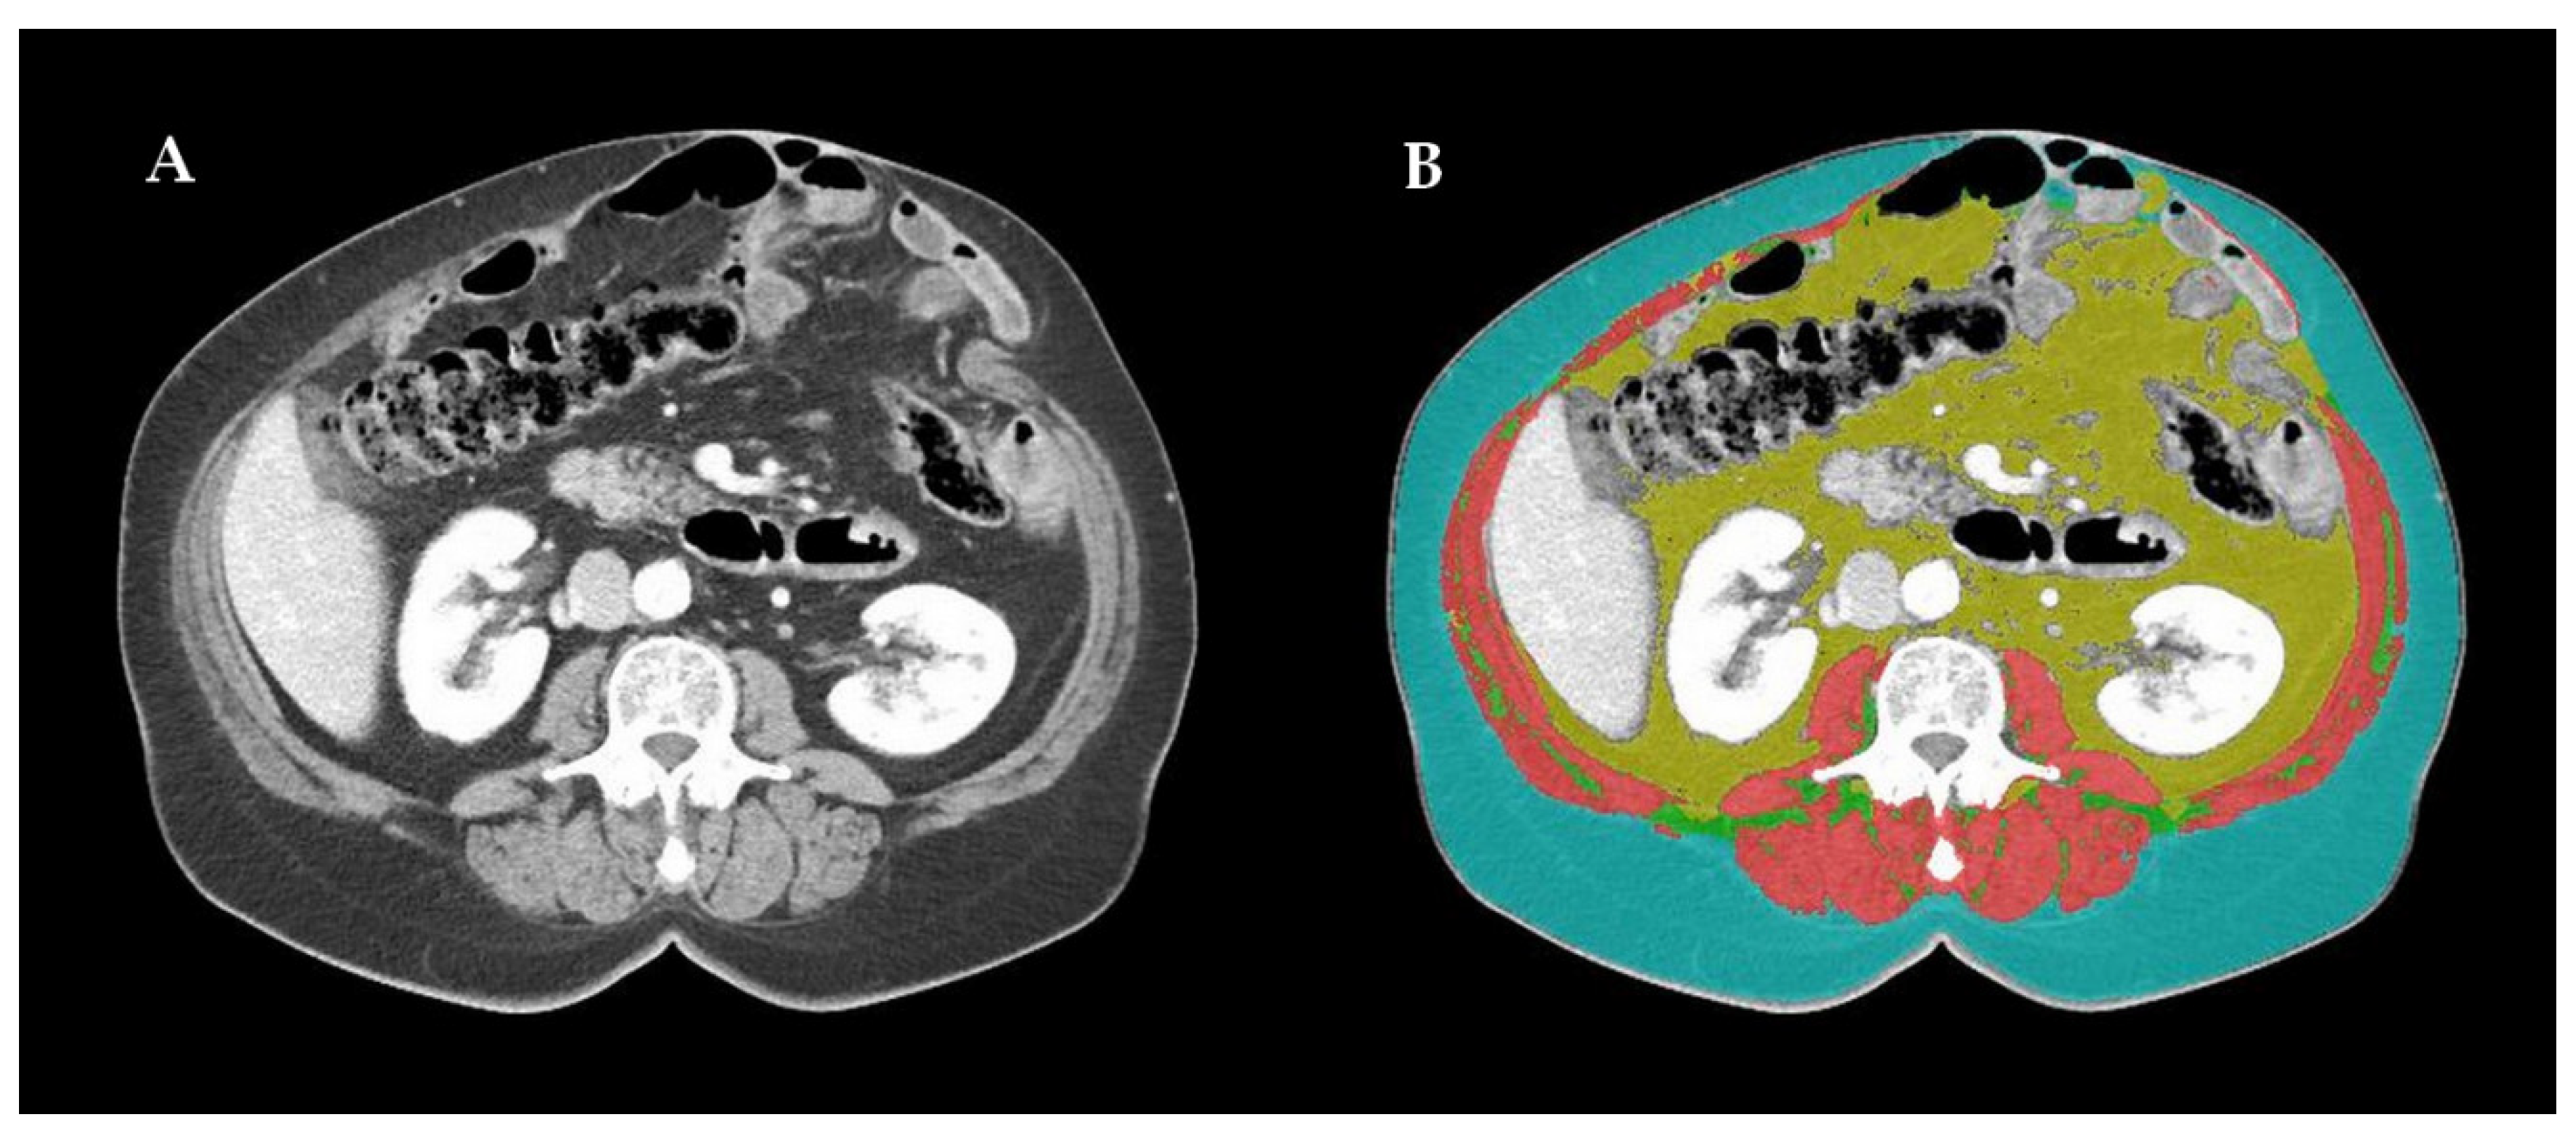

Imaging-based sarcopenia assessment was carried out by an experienced radiologist using dedicated automatic software: DAFS (Data Analysis Facilitation Suite) ver. 2.0.5 (Voronoi Health Analytics, Vancouver, Canada) with the ABACS (Automatic Body composition Analyzer using Computed tomography image Segmentation) module provided by Voronoi Health Analytics, Canada (2020). Some non-optimal segmentations were re-edited using open-source software 3D Slicer ver. 4.11 (3D Slicer, Boston, Massachusetts, USA). As the third lumbar vertebra (L3) has long been established as a standard landmark, two consecutive CT images, extending at least from L3 to the iliac crest, were chosen to measure the muscle cross-sectional area. Skeletal muscles were identified and quantified based on Hounsfield Unit (HU) thresholds. All the selected CT scans were contrast-enhanced in the venous phase. The L3 region contains psoas, paraspinal and abdominal wall muscles. The L3 SMI was determined as a ratio of the skeletal muscle area (SMA; cm2), contoured at the level of the L3 CT scan, to the patient’s height squared (m2) [8,9]. An example of this procedure is presented at Figure 1.

Figure 1. (A) Example of contrast-enhanced computed tomography scan of the third lumbar vertebra (L3) region in the venous phase (contains psoas, paraspinal and abdominal wall muscles); (B) image processed by Data Analysis Facilitation Suite ver. 2.0.5 by Voronoi Health Analytics, Vancouver, Canada with the Automatic Body composition Analyzer using Computed tomography image Segmentation module provided by Voronoi Health Analytics, Canada (2020); non-optimal segmentations were re-edited using open-source software 3D Slicer ver. 4.11 by 3D Slicer, Boston, MA, USA; skeletal muscles (pink) are separated from intra-abdominal fat (yellow) and subcutaneous fatty tissue (blue).